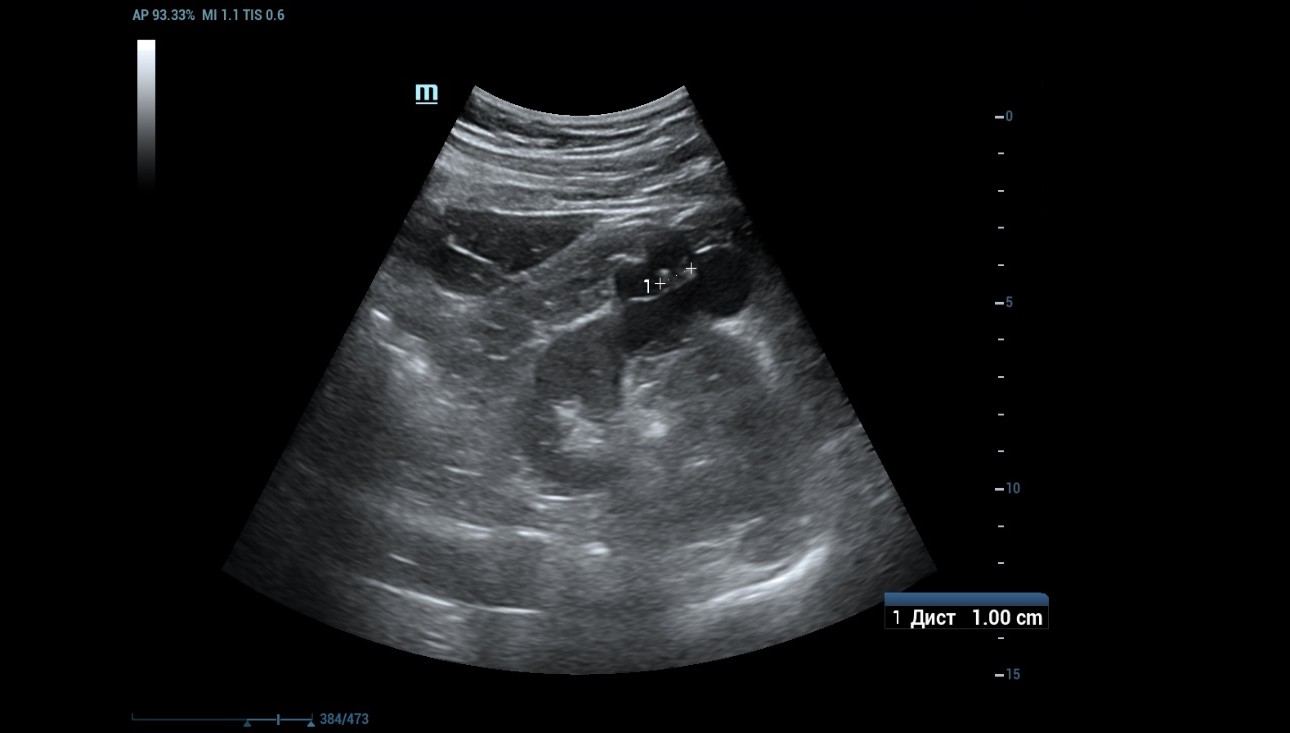

1) B-mode and Power Doppler mode imaging

An ultrasound examination was conducted using a Resona 7 ultrasound machine (Mindray, China) with the SC5-1U transducer. A cystic lesion measuring 46x35 mm in the middle part of the right kidney was found with multiple septa measuring up to 2 mm thick. When scanning the right kidney, a cystic mass with clear, even contours, 46 x 35 mm in size with multiple thick partitions (about 4 partitions) is visualized in the middle part of the cortex. It is homogeneous and anechoic within the cystic mass. A hyperechoic node measuring 10 mm in length was seen protruding into one of the cystic partition (Figure 1 and 2).

Figure 1: B-mode image showed a cystic mass in the right kidney.

Figure 2: A hyperechoic node measuring 10 mm in length was seen protruding into one of the cystic partition.